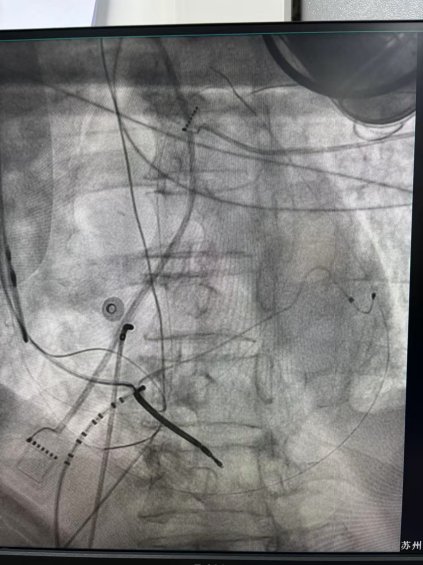

干穿心包进入外膜标测

王林林主任医师谨慎操作,成功进入心外膜达到病变位置。术中,患者反复自发多形态室速,且转为室扑,同时出现血流动力学不稳定,需多次电除颤方能终止发作,标测难度极大。这就要求医疗团队必须在有限的标测时间内精准定位室速消融靶点,并结合心内外膜基质特征制定消融策略。经针对性消融后,患者未再自发室速,且室性早搏转为单一形态,经判定为右心室乳头肌来源,随即予以一并消融。术后经心室程序电刺激验证,室速未再被诱发。